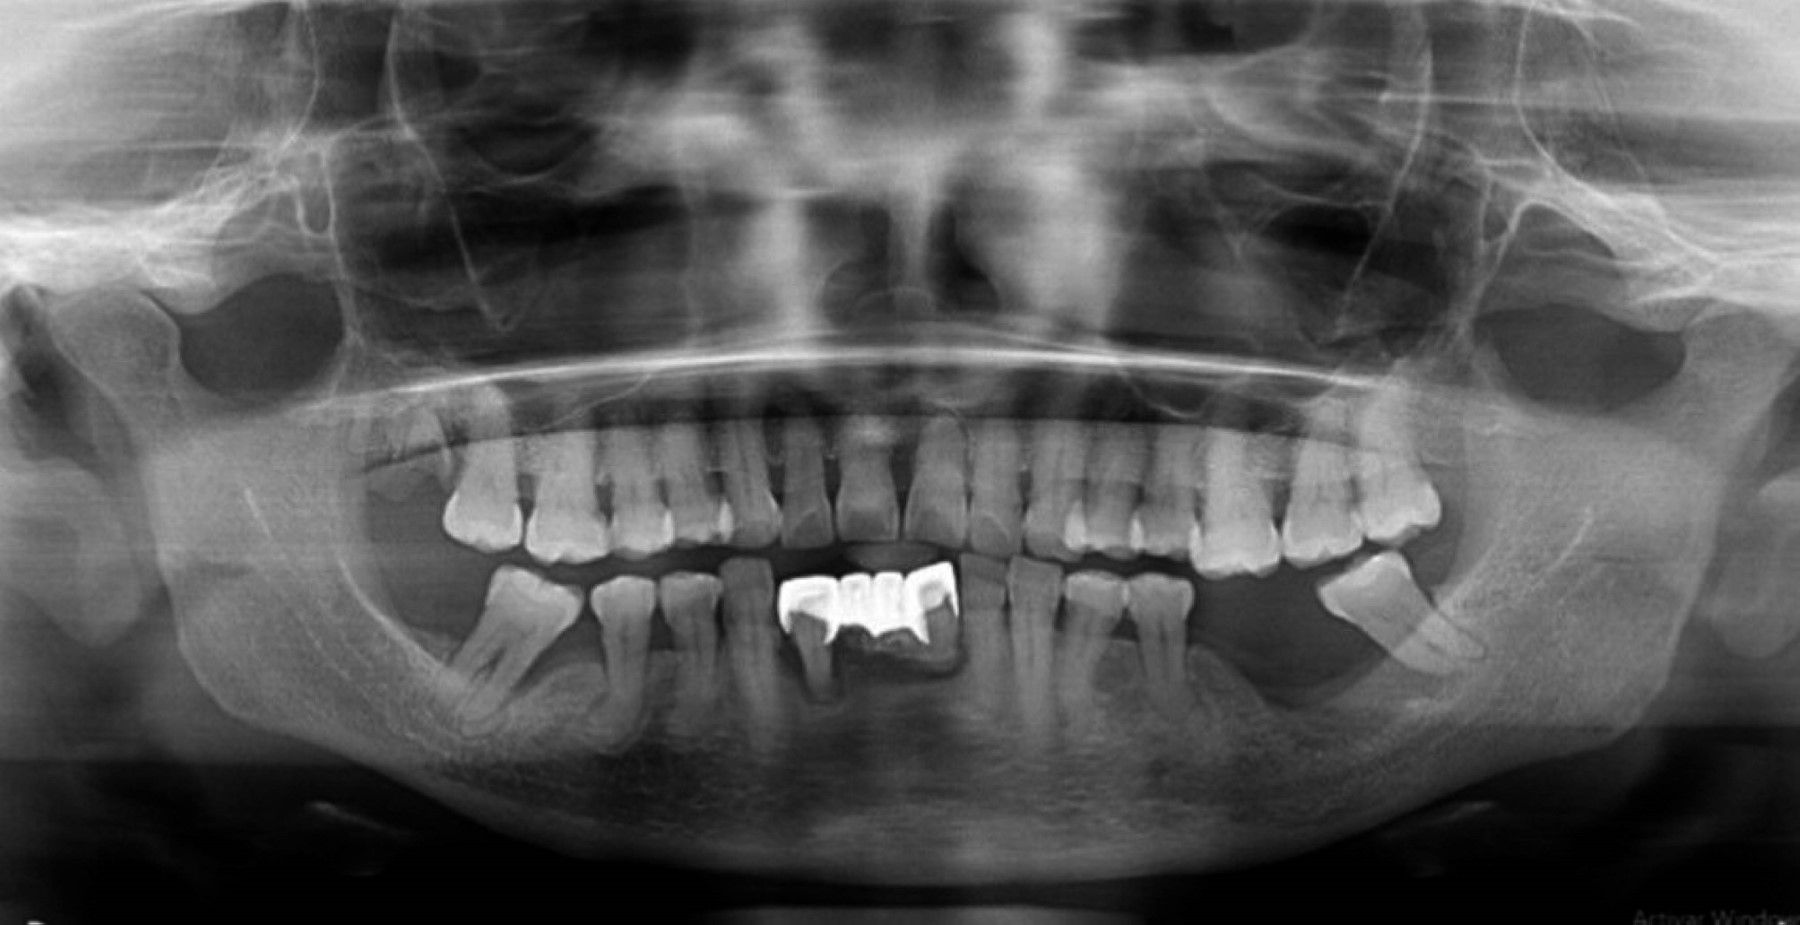

En la ortopantomografía se reveló una zona osteólisis de bordes irregulares, delimitada por un borde radiolúcido que denota presencia de secuestro óseo al mismo nivel de la secreción, sugerente de MRONJ (Figura 1).

La paciente acude a cita de control, refiriendo disminución de dolor; radiográficamente continúan signos de osteólisis (Figura 2). Se continúa tratamiento farmacológico y colutorios por cuatro semanas más.

Figura 1

Figura 2